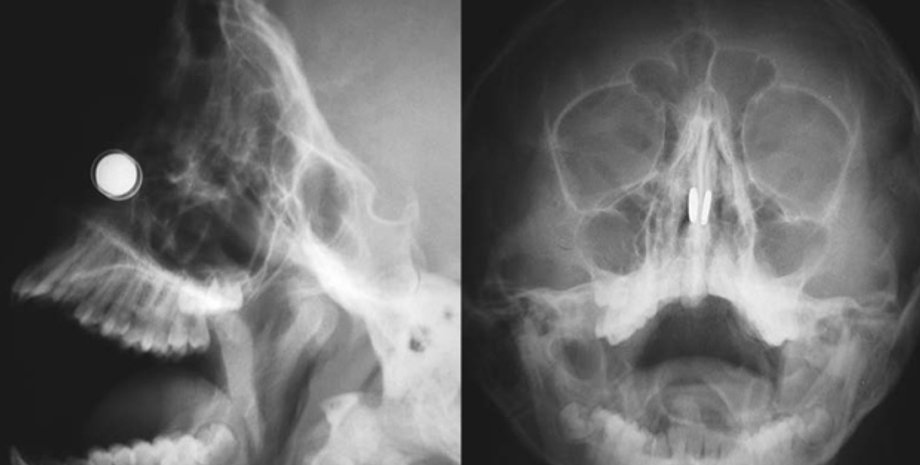

Фото: The New England Journal of Medicine

Сперва он прицепил магниты к мочкам ушей, а потом засунул пару магнитов в нос, соединив их с другой парой, закрепленной снаружи носа. Но, когда он снял внешнюю пару, внутренняя соединилась и застряла. Ученый попытался вытащить ее при помощи двух оставшихся магнитов, но и эта затея провалилась. После 20 минут безуспешных попыток и беглого поиска в интернете он нашел решение – использовать больше магнитов. Он взял два оставшихся и сосредоточился на левой ноздре.

"Я тянул, пытаясь вытащить магниты, но они выскочили из моих рук и сцепились, - рассказал Рирдон. – Два магнита застряли в моей левой ноздре, а еще один засел в правой. К этому моменту магниты у меня закончились".

Предприняв еще пару неудачных попыток достать запчасти от своего изобретения, доктор сдался и отправился больницу. Медики извлекли 3 магнита из левой ноздри, после чего магнит в правой выпал сам. Хотя эпопея могла и на этом не закончиться, ведь, по словам Рирдона, в этот момент он едва не поперхнулся.